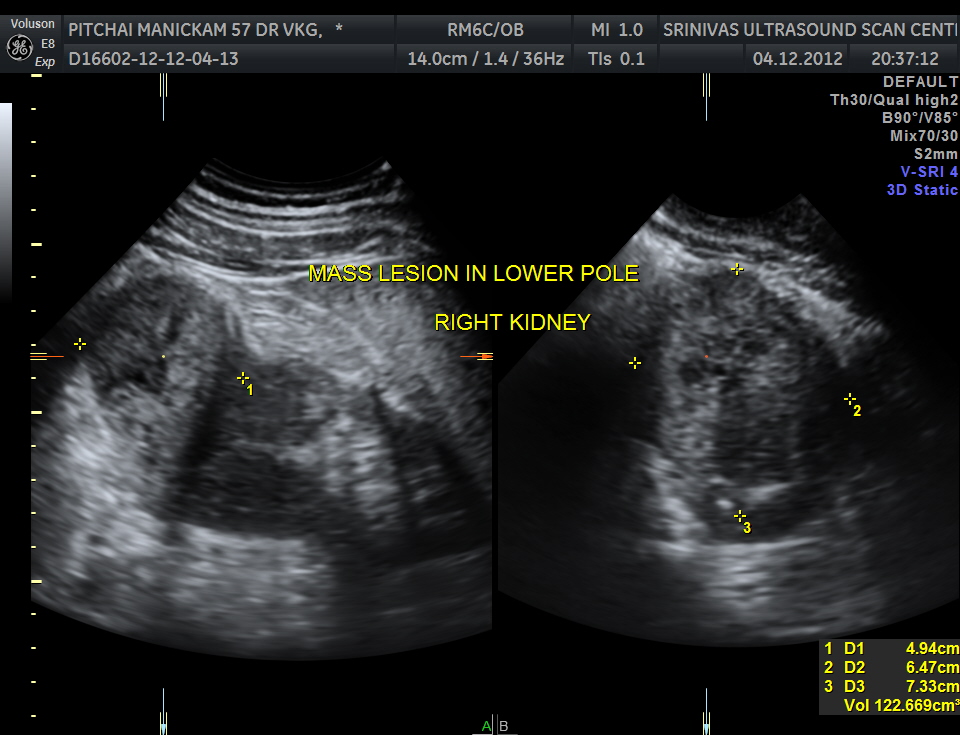

The right kidney pictures are given below. Mass lesion seen in the lower pole .

3 D images are given below.

The ultrasound diagnosis was a right renal mass – likely to be hypernephroma.